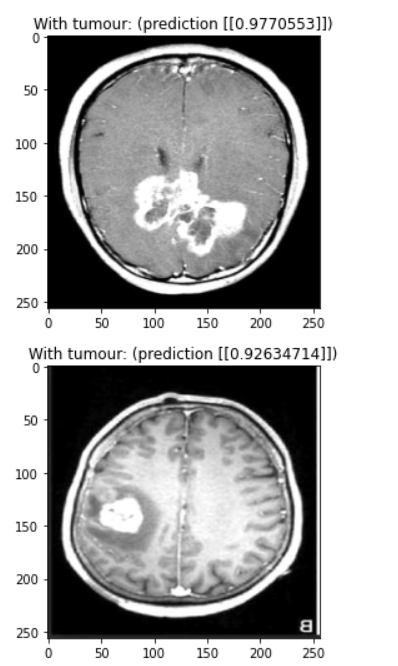

Our model is a convolutional neural network designed to detect brain tumours in MRI scans. You need a trained doctor to conclusively find a brain tumour, but our model can rule out scans that definitely don’t have a tumour and flag potential tumours for evaluation by a human doctor.

We used a combination of batch normalization and dropout to reduce overfitting, allowing us to train for over 80 epochs before noticing any overfitting. The main feature detection layers consist of convolutional layers with batch normalization where every second or third layer has a stride of (2, 2) to downsample the image. Each of these convolutional layers uses the ReLU activation function. We added a dropout of 0.2 in between the final convolutional layer and the output layer to reduce overfitting. We added this while struggling with a problem with our data, so it would be interesting to try removing this layer to see if it’s really necessary. Finally, our output layer is a single dense neuron with a sigmoid activation function. It would be interesting to experiment with using logits instead of a probability output.

Despite our different time zones, we were able to get together to work and accomplish the tasks. Utilizing different skill sets, we were also able to create a high-standard slide presentation and present with the passion that we have for the project. Additionally, after running into some issues, we were able to achieve a diagnostic accuracy of 90% in the time that we had.